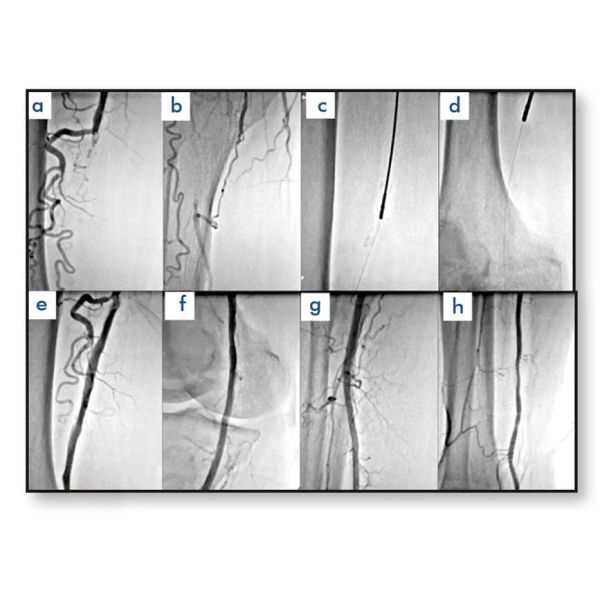

La aterectomía rotacional periférica TemREN es un sistema avanzado de aterectomía rotacional diseñado para mejorar los resultados en procedimientos de angioplastia con stent o globo. Su capacidad para reducir la carga de placa y lograr un diámetro luminal óptimo lo convierte en una herramienta clave en el tratamiento de lesiones vasculares calcificadas.

Además, permite la recanalización sin afectar el retroceso elástico, y ofrece una solución práctica gracias a su conjunto listo para usar, sin necesidad de equipamiento adicional previo a la intervención.

- Permite alcanzar el máximo diámetro de luz en procedimientos con globo o stent.

- Proporciona recanalización efectiva sin alterar el retroceso elástico.

- Reducción significativa de la carga de placa en lesiones complejas.

- Altas tasas de permeabilidad en lesiones calcificadas comparado con el stent primario.